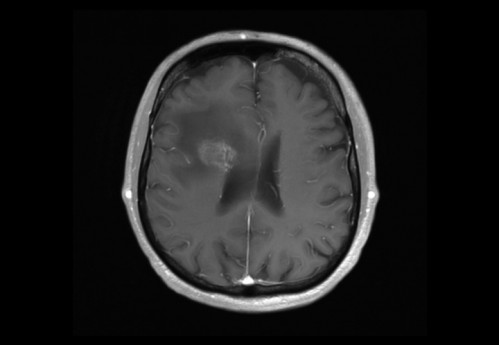

Sie behandeln einen 48-jähriger Mann, von Beruf Architekt. In der Anamnese erfahren Sie, dass er leidenschaftlich Gitarre spiele und er berichtet, dass ihm seit zwei Wochen in der rechten Hand die nötige Koordination fehle. Auch das Plektrum würde ihm immer wieder aus den Fingern gleitet.

Eine Magnet-Resonanz-Tomografie (MRT) des Kopfes wurde durch den ambulant behandelnden Neurologen bereits veranlasst.